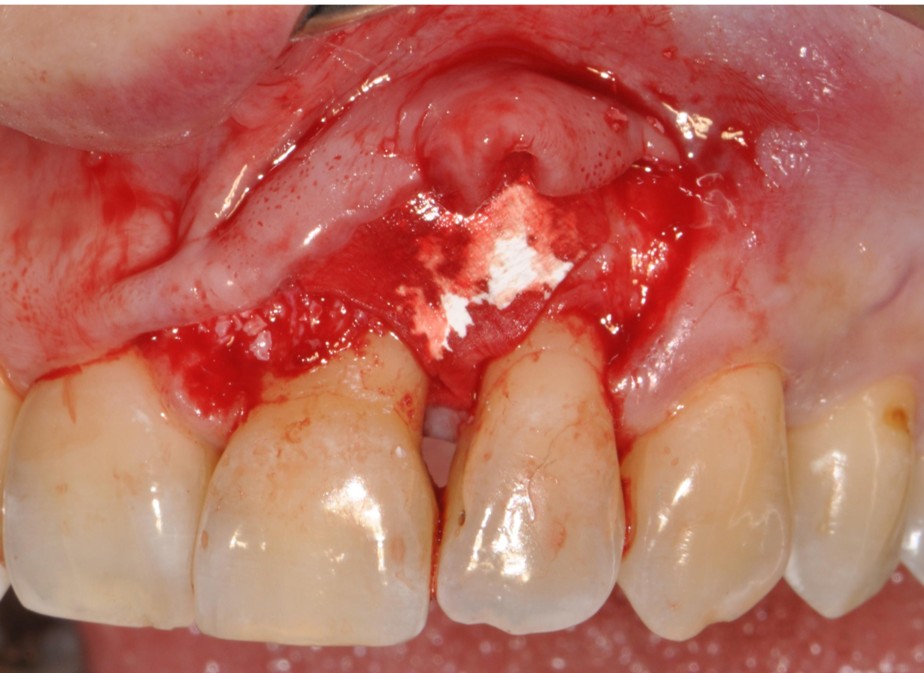

This workshop will explore the biological rationale, clinical decision-making, and surgical techniques involved in periodontal regeneration. While the primary focus will be on the regenerative management of infrabony defects, the discussion will be extended to more complex defect configurations. Particular emphasis will be placed on defect morphology, as well as on the selection of biomaterials and surgical approaches that critically influence clinical outcomes.

Special attention will be given to incision design and flap management, with a strong focus on papilla preservation techniques as a key element in achieving wound stability and primary closure. Through a combination of evidence-based lectures and detailed clinical case discussions, participants will gain a comprehensive understanding of how to optimize regenerative outcomes in daily clinical practice.

Key topics will include flap design, papilla preservation strategies, wound stability, soft tissue management, post-operative care, as well as the limitations and challenges of periodontal regeneration. Even in complex periodontal defects, a sound biological and clinical rationale for reconstruction and regeneration can often be identified.